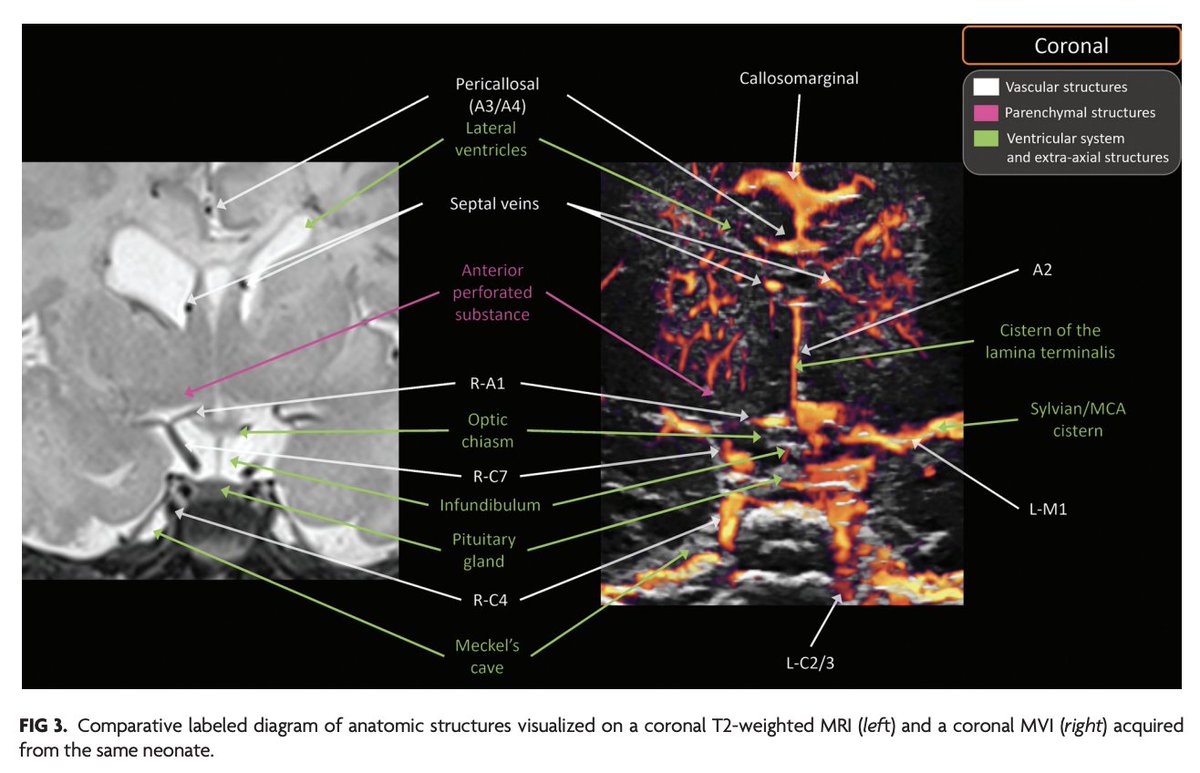

@PennRadiology @CHOPRadiology @PennMedicine @ChildrensPhila @The_ASPNR "MVI offers a safe, convenient, noninvasive approach to neurovascular assessment that eliminates the need for ionizing radiation or sedation and positions MVI as a useful technique for screening and subsequent evaluations of neurovascular pathologies."

"An Atlas of Neonatal Neurovascular Imaging Anatomy as Depicted with Microvascular Imaging: The Intracranial Arteries" https://t.co/ixEobV68qC

@PennRadiology; @CHOPRadiology; @PennMedicine; @ChildrensPhila; @The_ASPNR

1

19

88